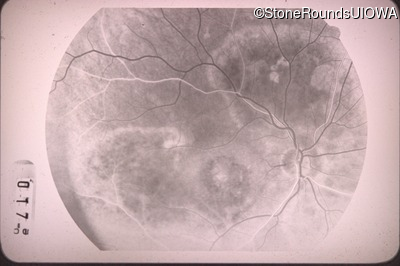

Fluorescein Angiography - Right - 20/100 -1

Exemplar